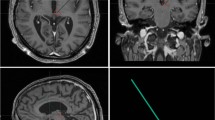

Before surgery, the patient underwent a 3T stereotactic MRI (Siemens, Malvern, Pennsylvania, USA), including axial T2-weighted and post-gadolinium (Gd) volumetric axial T1-weighted sequences. Pre-operative CM-Pf targets were determined from the mid-commissural point on anterior–posterior (AC-PC) aligned MRI images. Target planning for the central thalamus (intentionally aimed at the CM-Pf complex using traditional stereotactic methods) was optimized, based on the width of the third ventricle with final coordinates: 9.8 mm lateral, 9.5 mm posterior, and 2.8 mm ventral to the midcommissural point. Planned trajectories were inspected to be pre-coronal, start on top of a gyrus, and to avoid ventricles and blood vessels. 18F-fluorodeoxyglucose (FDG)-PET/CT brain imaging was performed on a Siemens PET/CT system (Biograph mCT FlowTrue-V-128), conform European Association of Nuclear Medicine guidelines, to confirm the presence of FDG-uptake in the center of the anticipated target area (see Fig. 4)43. More specifically, FDG images were acquired for 10 min, starting at 30 min after bolus intravenous injection, and low-dose CT was used for attenuation correction. Images were reconstructed iteratively with point‐spread function and time‐of‐flight modelling, and a 2‐mm full‐width at half‐maximum Gaussian filter. Planning, including fusion of the MRI and PET was done using Brainlab Elements software (Brainlab AG, Munich, Germany, version 3.2.0.281).